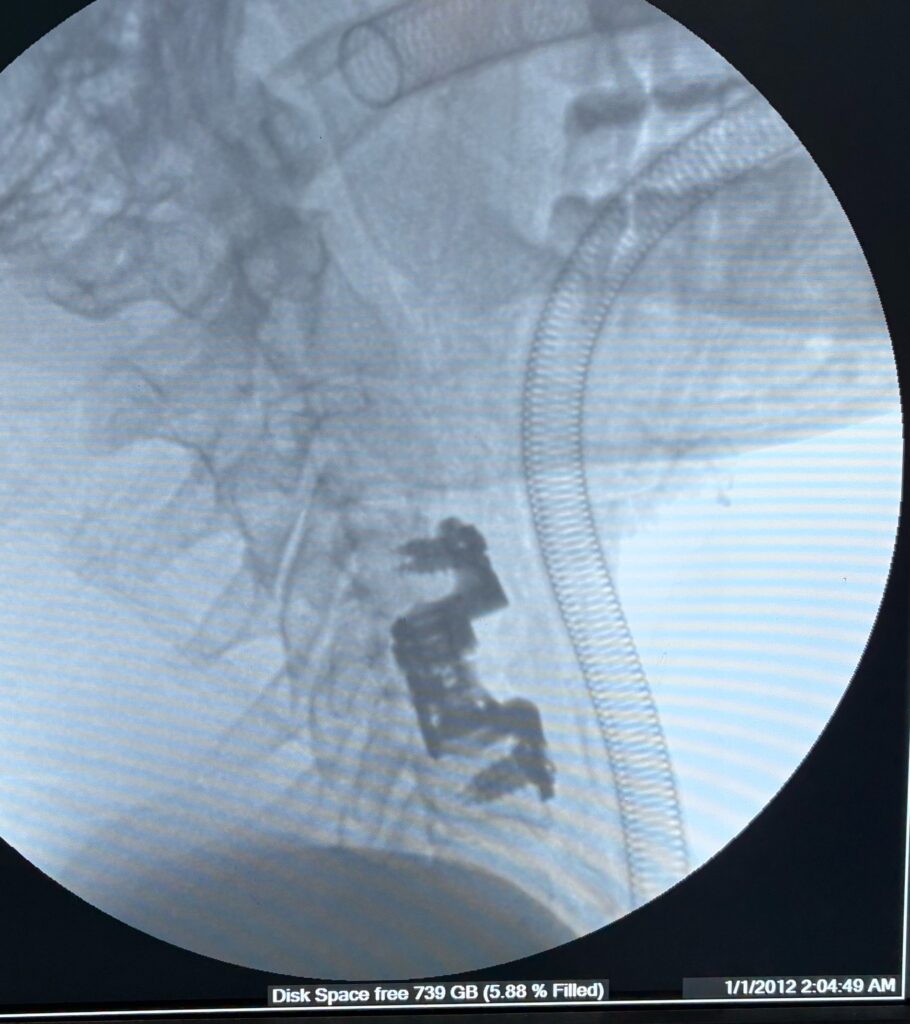

- Spinal fixation: To stabilize fractured bones

Modern spine surgery uses advanced techniques that improve safety and recovery time.

Cases treated by Spine Specialist Dr. Gaurav Sandeep Gupta